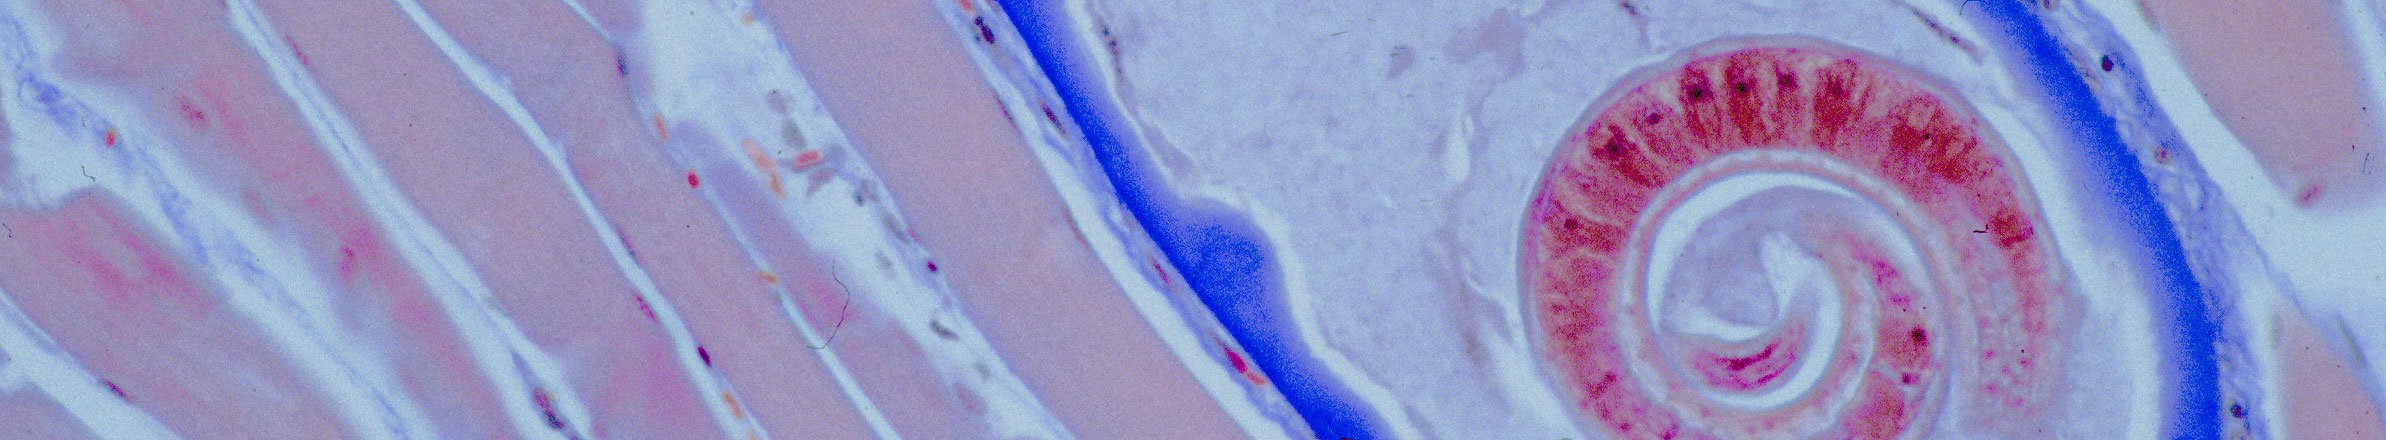

Auch wenn der Jäger keine bedenklichen Merkmale feststellt, muss beim Wildschwein jedes Alters, auch beim Frischling in Spanferkelgröße, eine gebührenbehaftete Untersuchung der Muskulatur auf Trichinen durchgeführt werden. Die Anmeldung dazu kann am Wohnort des Jagdausübungsberechtigten, aber auch in einem anderen Beschaubezirk erfolgen, wohin der Tierkörper verbracht wird. Die Entnahme der Proben aus dem Zwerchfell und vom Vorderlauf ist eine amtliche Handlung und somit vom Untersucher vorzunehmen. Vor Abschluss der Untersuchung und der Beurteilung "trichinenfrei" darf das Wildbret nicht verwertet werden.